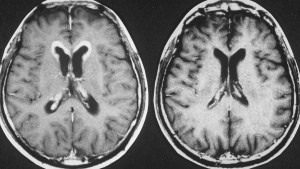

病理診断は困難ではありません。左側の写真のように,多くの場合にHE染色でtwo-cell patternと呼ばれる, 大型の腫瘍細胞と小型のリンパ球 (T cells) 浸潤の特徴的な病理像で診断がつきます。大型の腫瘍細胞は楕円形の大きな核に大きな核小体が特徴です。

弱拡像です。類円形で大型の核を有するgerm cell (胚細胞)類似の細胞と小型のリンパ球からなる腫瘍で、two cell patternと呼ばれています。